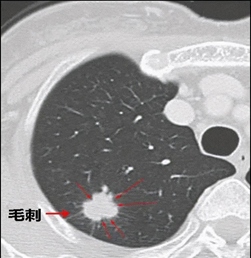

毛刺、分叶状结节—高危

恶性几率很高